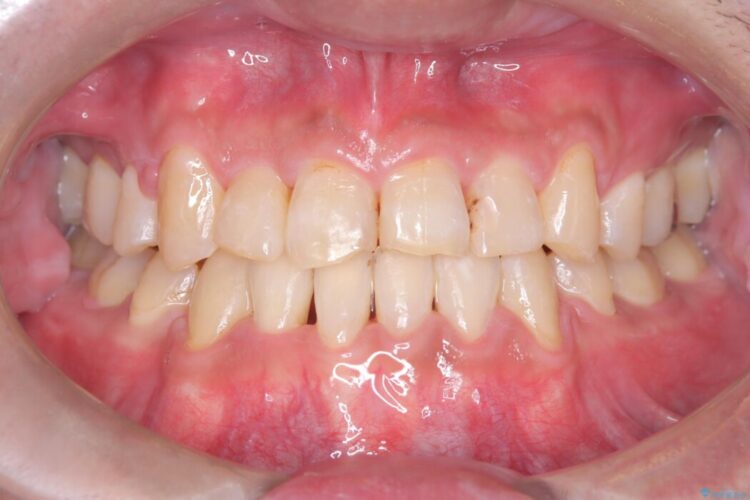

治療後について

骨格性Ⅲ級を示しましたが、構成咬合位がとれたことから反対咬合と叢生改善のため、上下左右第一小臼歯を抜歯しワイヤー矯正を行いました。途中、バイトアップを行っています。